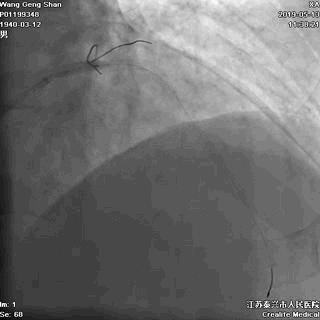

03 第一第二对角支保护

对角支导丝到位

左冠共计5根导丝

前降支近段支架植入后用非顺应性球囊高压扩张